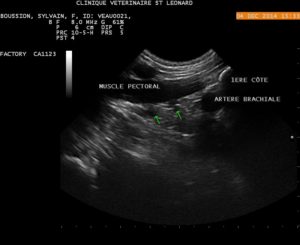

Avant injection, les flèches vertes montrent les nerfs du plexus brachial, sous le muscle pectoral, en coupe transversal.

Après injection de lidocaine, les nerfs sont maintenant au contact, ou entouré de lidocaine et le membre (en tous cas le coude) anesthésié.